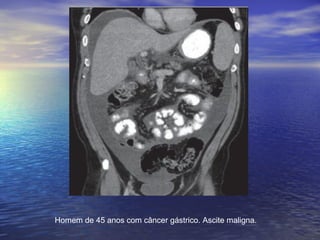

Homem de 45 anos com câncer gástrico. Ascite maligna.